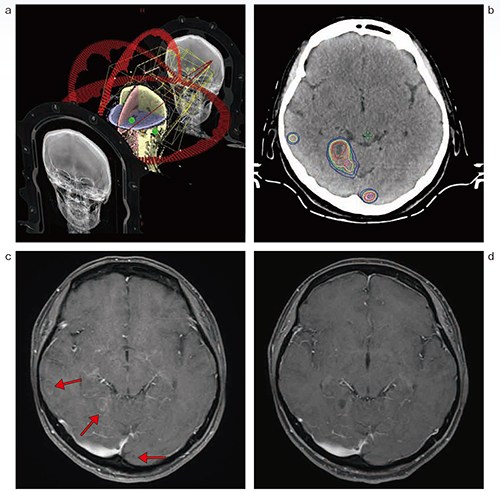

12病変であった(図2)。それらの検証に関しては,いずれも絶対線量検証にて線量誤差3%以内,線量分布検証にて3%/2mmのガンマパス率90%以上を得られている。

図2 HyperArcでの治療の一例(肺がん・脳転移)

a:4アークでのHyperArc

b:線量分布図

c:治療前のMRI(ガドリニウム造影T1強調画像)

d:治療終了5か月後のMRI(ガドリニウム造影T1強調画像)

PTV-D98%,35Gy/5回の治療を12か所に行った例。5か月後のMRIで病変の縮小,消失および内部の壊死が認められた。